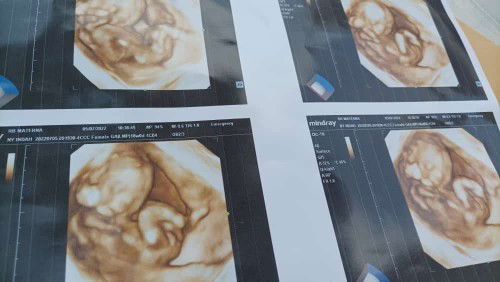

Alhamdulilah abis USG Pertama Kali yang 4D dede mungilnya sehat JK Perempuan DJJ 156 BJ 223 Gerakan Aktif UK 18W1D Beda Sama HPHT 2W Tapi Lebih Akurat Yang Di USG kata dokternya . HPL Des 2022 . Sama sama berdoa Buat Bunda Bunda yg HPL nya Desember 2022 semoga lancar sampai lahiran. Aamiin Yarabbal Alamin . #firstmom #firstbaby